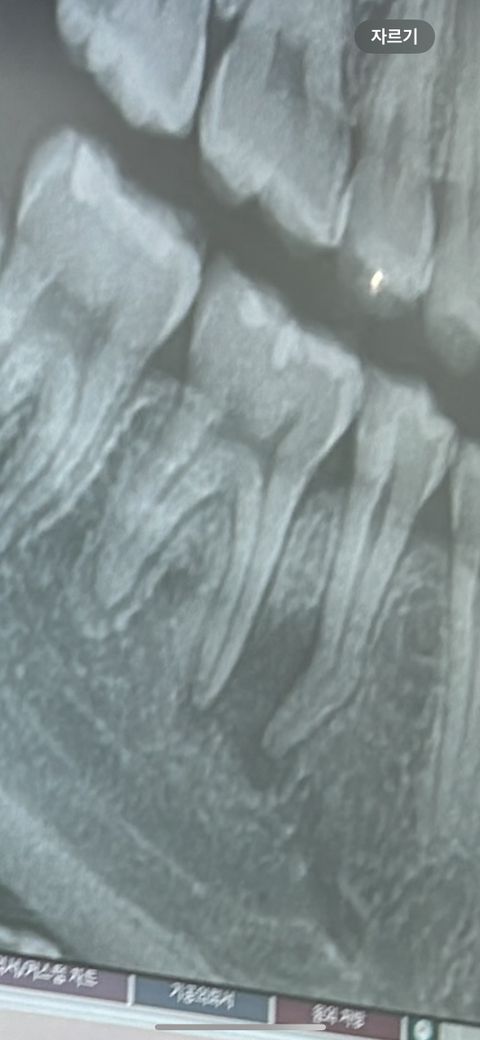

다른 치료는 없는거겠죠 사진에 보이는게 염증맞너요?

• 1번 째 사진

뿌리상에 염증이 보이기 때문에 신경치료를 받으시는 것이 일반적인 치료방법입니다. 치과 가보시면 됩니다.

사진으로는 신경관에 감염이 되어 치근단에 염증이 생긴 것으로 보입니다.

신경치료후 크라운 치료를 해야 할것으로 생각됩니다.

엑스레이 사진상 염증이 있고 그리고 증상을 봤을때 신경치료는 불가피해보입니다 염증은 오래전부터 진행되어 온 것 같습니다

사진상으로 보면 치아 뿌리끝에 염증이 잇습니다. 신경치료를 하셔야될것같은 치과에 문의를 해보시는게 좋을것같습니다.